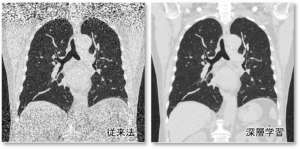

✔ 深層学習を利用したノイズ低減法

・従来型のノイズ低減フィルタと比較して、空間分解能の劣化を抑えつつノイズを低減することができる